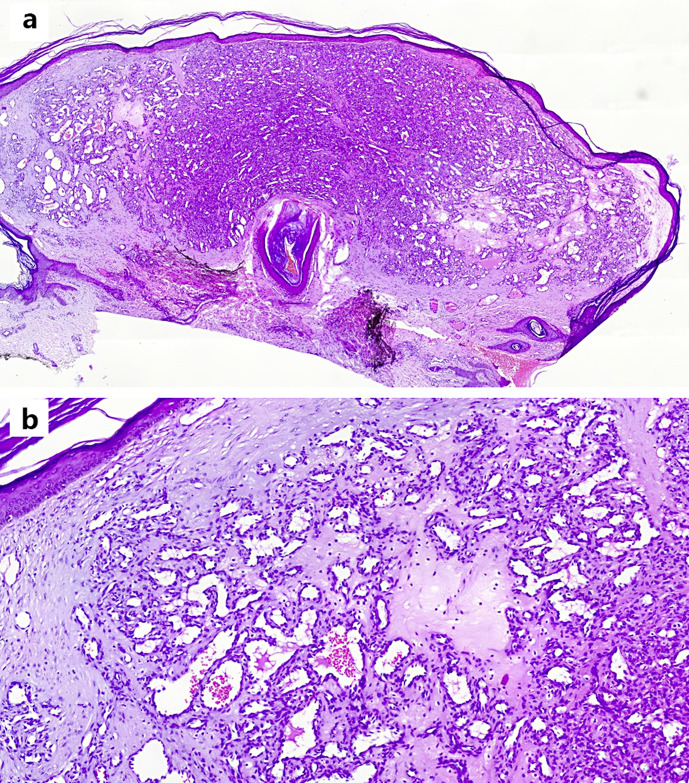

导言:化脓性肉芽肿临床表现为皮肤或粘膜上迅速生长、易碎的红色丘疹,通常小于10毫米,经常因溃疡而出血。在感染 COVID-19 或接种 COVID-19 疫苗后,曾有包括化脓性肉芽肿和樱桃状血管瘤在内的血管增生性疾病的报道:在此,我们报告了一名 52 岁的女性患者,她在接种第二剂 COVID-19 疫苗 3 周后出现弥漫性皮肤糜烂:据我们所知,这是首例接种 COVID-19 疫苗后出现糜烂性 PG 的病例。口服普萘洛尔和 PDL 激光治疗是在电灼治疗效果不佳的情况下进行的,在开始治疗的 6 周内取得了良好的反应,即新皮损停止形成,大面积皮损面积缩小。

Introduction: Pyogenic granuloma presents clinically as a rapidly growing, friable, red papule of skin or mucosa, commonly measuring less than 10 mm with frequent bleeding due to ulceration. Angioproliferative diseases including pyogenic granuloma and cherry angioma have been reported during COVID-19 infection or following COVID-19 vaccination.

Case presentation: Here, we report a 52-year-old female patient who developed diffuse skin eruptions 3 weeks after the second dose of COVID-19 vaccination.

Conclusion: As per our knowledge, this is the first case of eruptive PG following COVID-19 vaccination. Oral propranolol and PDL laser therapy were administered after obtaining inconvenient results from electro-cautery, and there was a good response within 6 weeks of starting therapy, defined by the cessation of new lesion formation and a decrease in the size of large lesions.